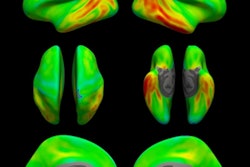

In a large multicenter prognostic study, a group of Swedish, South Korean, and U.S. researchers examined the accuracy of flortaucipir F-18 and RO948 F-18 PET for detecting tau pathology in patients with Alzheimer's disease dementia, mild cognitive impairment, and normal cognition. The team found the radiotracers performed significantly better in all groups at predicting cognitive changes when compared head-to-head against MRI and amyloid PET imaging.

In this study, Ossenkoppele and colleagues assessed the prognostic accuracy of baseline flortaucipir F-18 and RO948 F-18 PET for detecting tau pathology in individuals across the Alzheimer disease clinical spectrum and compared the tracers against established MRI and amyloid PET markers.

The investigators used the measures of baseline flortaucipir F-18/RO948 F-18 PET retention within a temporal region of interest, MRI-based Alzheimer's disease-signature cortical thickness, and amyloid PET centiloids -- along with models adjusted for age, sex, education, and cohort -- to predict changes in the MMSE. They assessed performance using R2 values, a statistic that describes how well a model fits the task.

Ossenkoppele and colleagues found that flortaucipir F-18 uptake predicted longitudinal changes in MMSE. This uptake effect was stronger than for Alzheimer's disease-signature cortical thickness and amyloid PET across all participants, including the amyloid-positive group with mild cognitive impairment and the amyloid-positive group who were not cognitively impaired.